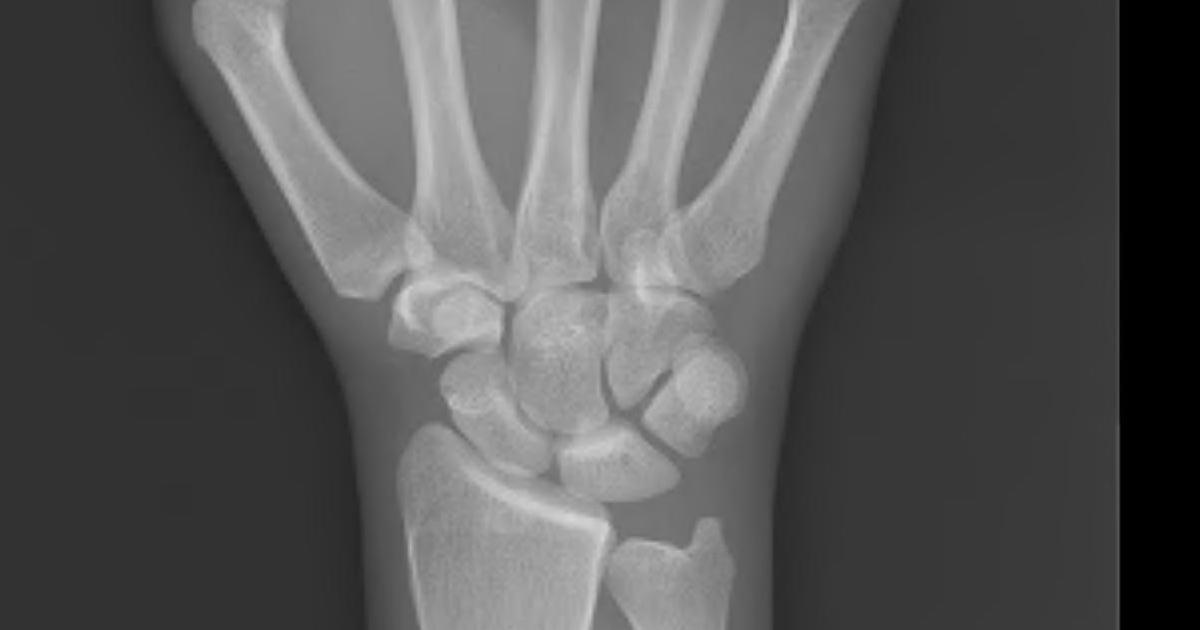

Wrist pain might be simple discomfort, but it can also be an indicator of a serious medical condition. Wrist pain often comes with other symptoms. Individuals might have swollen fingers, numbness or tingling, sharp pains in the hand, warmth near the joint, and difficulting making a fist. If patients notice their wrist is warm and red and they have a fever more than oen hundred degrees Fahrenheit, they need to call a doctor immediately. To diagnose the reason why individuals are feeling wrist pain, the doctor will likely have patients bend their affected wrist for a minute to test if numbness or tingling develops. They might also take x-rays to see how healthy the patient's bones and joints are.

Kienbock's disease is rarer than carpal tunnel syndrome. It disrupts the blood as it is on the way to the carpal bones in the wrist. The lunate, one of the carpal bones in the wrist, is in the center of the wrist and it is vital for wrist movement. In the beginning, the disease causes pain. However, as it progresses, it causes the tissue and bone to die, resulting in the immobility of the wrist and arthritis. Typically it will only affect one wrist. If patients notice they have tenderness over the wrist bone, stiffness, lack of grip, swelling, or difficulty turning the hand upward, they might have KIenbock's disease. It typically progresses through four stages, and it is believed to progress quickly. The first stage might not show damage in x-rays, but by the fourth stage, the lunate has deteriorated. When the lunate deteriorates, it causes arthritis in the wrist, and it can be debilitating in the final stage.

Wrist trauma can also be the source of significant wrist pain. Typical wrist injuries include sprains, fractures, dislocating the PIP joint, and other injuries to the bone. Sprains occur when the ligament in the joint is damaged. It connects the bone to the tissue, and it is typically damaged when there is enough force. There are several different grades of sprains including minor tears and entire ruptures. Wrist sprains happen when individuals catch themselves when falling by putting their hands out. This causes individuals to land hard on their palm, causing their wrist to bend backward and straining the ligaments. The bones in the joint can also become fractured or dislocated. Fractures can be common sports injuries. Typically this is the fracture of the scaphoid bone, one of the small bones in the wrist.